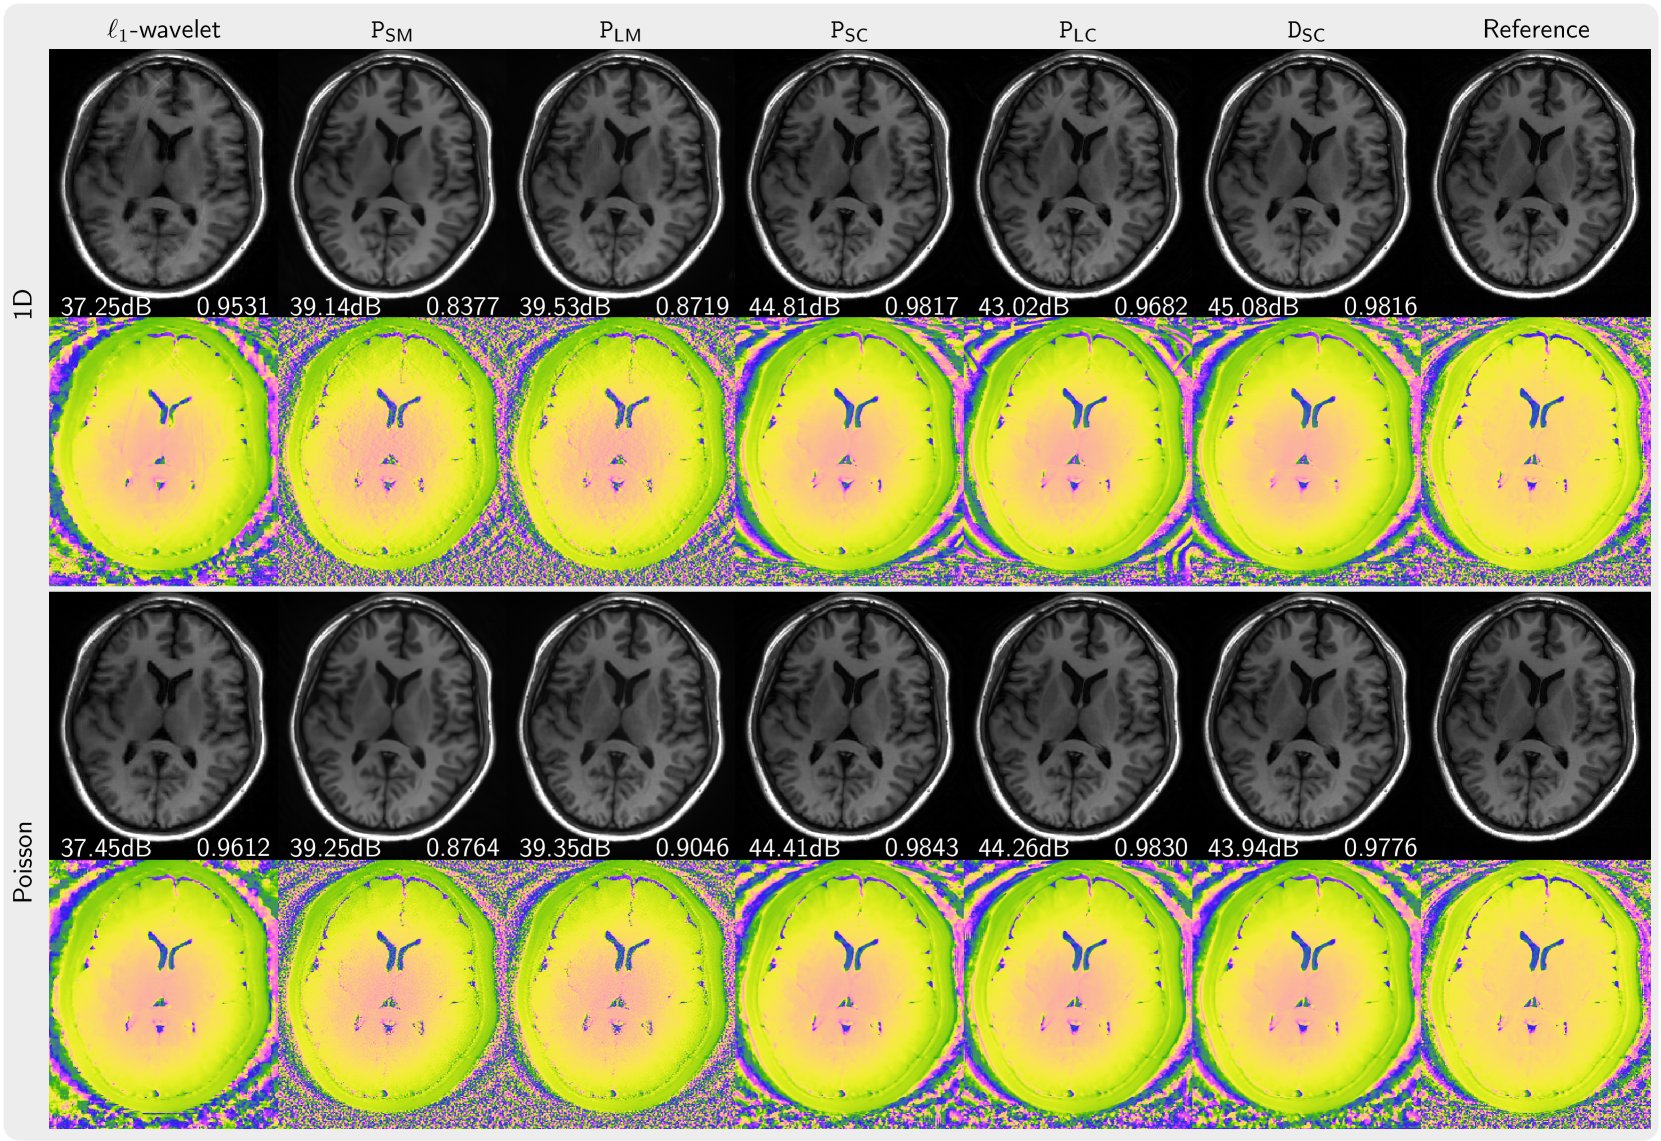

Figure 3 presents the magnitude and phase of images that are reconstructed using PICS with priors trained from magnitude image, complex images with preserved phase, and complex images with generated using our phase augmentation method While the priors PSM and PLM trained from magnitude images can remove folding artifacts introduced by undersampling, they exhibit over-smoothing of the magnitude as indicated by its lower PSNR and SSIM values and also demonstrates poor capabilities in denoising the phase. In contrast, the prior PSC trained on complex-valued images performs much better. Furthermore, the priors PLC and DSC trained on phase-augmented images and perform almost as well. Very similar results were obtained for NLINV as shown in Figure 4. In Figure 5, the k-space is sampled using 2 ×\times× 3 pattern. We observed artifacts (red arrow) introduced by the priors trained from magnitude-only images reconstructed with PICS method, but not with NLINV method. Under all investigated conditions, the priors trained on complex-valued images outperform the reconstruction with 1subscript1\ell_{1}roman_ℓ start_POSTSUBSCRIPT 1 end_POSTSUBSCRIPT-wavelet regularization.

Refer to caption

Figure 3: Comparison of images reconstructed using PICS using the priors PSM, PLM, PSC, PLC, DSC in comparison to an 1subscript1\ell_{1}roman_ℓ start_POSTSUBSCRIPT 1 end_POSTSUBSCRIPT-wavelet reconstruction and a reference (c.f. error maps in the supplementary). The top two rows (1D) present the results for 5-fold acceleration along phase-encoding direction with 30 calibration lines. The bottom two rows (Poisson) show the results using a Poisson-disc acquisition of 8.2x-undersampling. PSNR and SSIM values are shown in white text.